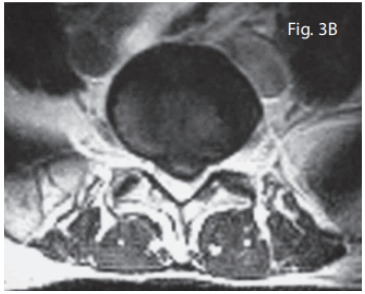

During this trial of divergent care, plain film radiographs and MR images of the lumbar spine were obtained. The radiographs were performed in the weight-bearing position and included anteroposterior and lateral projections. They revealed a slight levorotatory lumbar scoliosis and significant flattening of the lumbar lordosis. These films suggest an acute clinical presentation. The disc space at L5/S1 demonstrated approximately 50% loss of height; no other signs of degenerative change were seen (i.e. sclerosis, spondylophytosis) (Fig. 2). The MRI was performed on an upright unit and the images were taken in the neutral seated (weight-bearing) position using standard imaging protocols. The T1- and T2-weighted sagittal and axial images were reviewed by a chiropractic radiologist and collectively revealed discal dehydration and desiccation at the L4/5 level with underlying degenerative bulging of the disc. There was no disc herniation at this level. A left paracentral disc herniation (extrusion) was present at the L5/S1 level, which posterolaterally displaced the left S1 nerve root. An area of bright signal intensity within the disc herniation represents an annular tear. There was approximately 50% loss of disc height at the same level with a corresponding degenerative loss of signal intensity and evidence of discal desiccation (Fig. 3A and B).